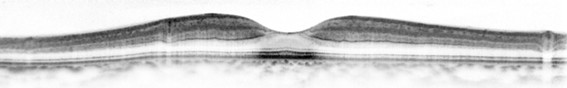

さらに、光干渉断層計(OCT)で網膜のむくみや血流の低下を確認します。